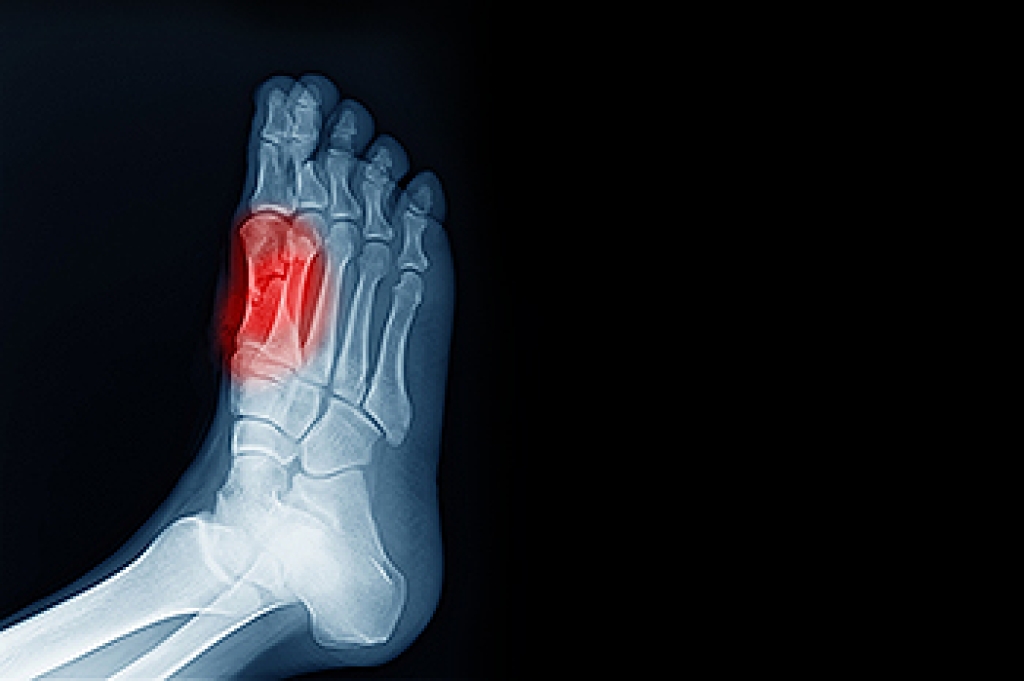

Corns: What Are They? and How Do You Get Rid of Them?

Corns can be described as areas of the skin that have thickened to the point of becoming painful or irritating. They are often layers and layers of the skin that have become dry and rough, and are normally smaller than calluses.